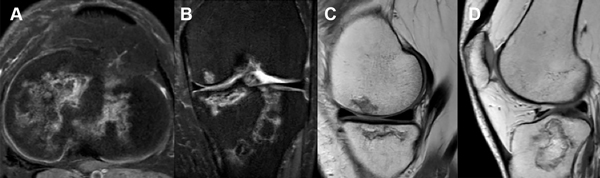

Realizamos resonancia magnética de control a los veinticuatro meses. Tanto en los cortes axiales, sagitales como coronales de la rodilla derecha (fig. 9) como de la rodilla izquierda (fig. 10) no evidenciamos grandes cambios en relación a una posible mejoría, tampoco una probable progresión de la enfermedad en relación con las múltiples imágenes compatibles con infartos óseos que ya veíamos en la RM preoperatoria.

Figura 9: RM rodilla derecha. A) Corte axial. B) Corte coronal. C y D) Cortes sagitales. Focos osteonecróticos, tanto en fémur como tibia, ya conocidos en imágenes preoperatorias, sin grandes cambios evolutivos.

Figura 10: RM rodilla izquierda. A) Corte axial. B) Corte coronal. C y D) Cortes sagitales. Múltiples infartos óseos difusos ya diagnosticados en imágenes preoperatorias, sin grandes cambios evolutivos.